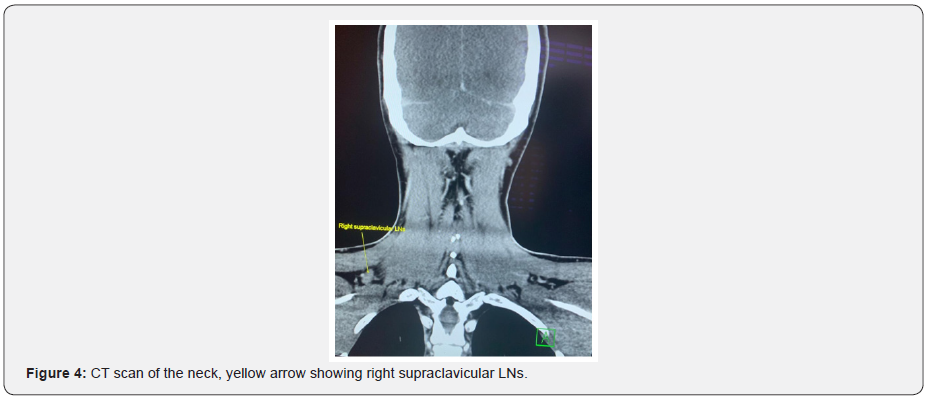

An ultrasound neck was done and revealed, multiple enlarged lymph nodes in the right supraclavicular and deep cervical groups. The largest measures 19x10mm and some of the nodes showed distorted hilum. Another enlarged lymph node noted in the left submandibular group measures 15x8mm. Both thyroid lobes and isthmus were normal except for a nodule in the right lobe, which has the following criteria: R1 seen at the lower part of the lobe measures about (10x8x9.5mm) with mild surrounding vascularity, according to the ACR TI RADS its of TR5 which needs FNAC. ACR TI RADS CLASSIFICATION: it is mixed cystic and solid, hypoechoic, taller than wide, smooth, and punctate echogenic foci, which is highly suspicious for malignancy. An ultrasound guided fine needle aspiration of the thyroid nodule and the lymph nodes was done. The thyroid nodule showed a well-differentiated papillary thyroid cancer, and the lymph nodes showed a high-grade malignant tumor that needs a complete lymph node biopsy. Flow cytometry of the sample showed predominantly T-lymphocytes.

A pan CT was done, revealed multiple enlarged right upper and lower deep cervical lymph nodes in the neck, they are well defined, and homogenous, the largest measures about 19x11mm, few other small left upper and lower deep cervical and bilateral supraclavicular lymph nodes noted. The largest one measures about 10x6mm, also showed normal CT features of the nasopharynx, oropharynx, larynx, supraglottis, hypopharynx, vocal cords, pterygo-palatine, and pterygo-maxillary fossae, parapharyngeal and retropharyngeal spaces, parotid and submandibular glands, the rest of the paranasal sinuses were unremarkable.